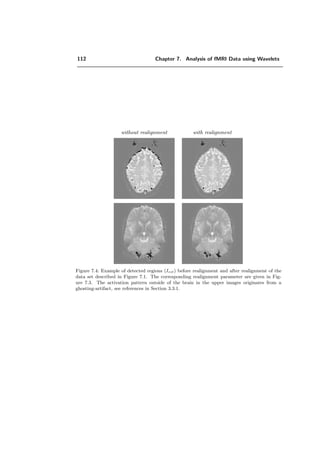

a) without realignment b) with realignment

Figure 2.12: Example of the influence of realignment. The activation in the brain was caused

by a visual task. a) Detection of activation based on raw data with the algorithm developed in

this work. Some of these detected areas are caused by movement artifacts, in particular the one

on the border in the upper brain region. b) Detection of activation based on data which were

realigned with SPM99. Most of the detected areas which were caused by movement artifacts

disappear.